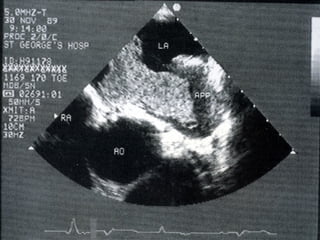

• Echocardiogram, CXR

DIAGNOSIS • Pulse palpation •12 lead ECG • Holter monitoring • Others • Echocardiogram, CXR • TFT, Electrolytes, Clotting, LFT,CBC